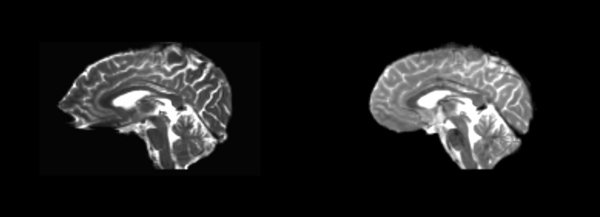

Linear

- 53-t2 -> 31-t1 = lin1

- lin1 -> 53-t2 = lin2

The image shows lin2 and 53-t2 side by side. The image shows there appears to be some change beyond loss of detail, possibly a L-R shift in the front.